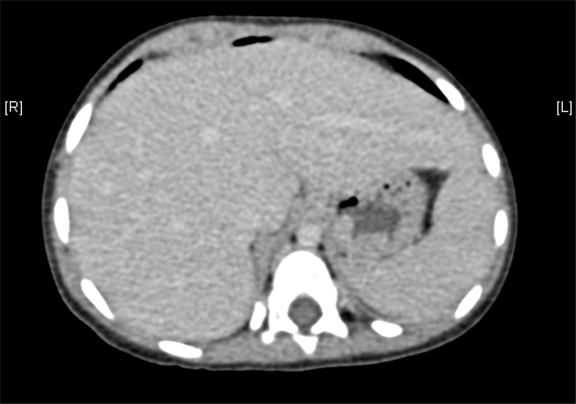

术前CT检查:

静脉期

上腹部增强CT提示肝门处占位性病变,考虑腹膜后肿瘤可能性大,畸胎瘤? AFP 11.38ng/ml

将0.625mm双源薄层CT资料的静脉期和动脉期Dicom格式文件导入海信CAS系统。

通过调节窗宽窗位调整CT序号,对肿瘤、肝实质,胆囊,下腔静脉,肿瘤,肝动脉、门静脉及肝静脉等进行三维重建;系统自动计算肿瘤体积和肝脏体积。